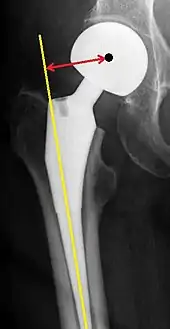

Post-operative projectional radiography is routinely performed to ensure proper configuration of hip prostheses.

The direction of the acetabular cup influences the range of motion of the leg, and also affects the risk of dislocation.[9] For this purpose, the acetabular inclination and the acetabular anteversion are measurements of cup angulation in the coronal plane and the sagittal plane, respectively.

Acetabular anteversion is normally between 5 and 25°.[9] An anteversion below or above this range increases the risk of dislocation.[9] There is an intra-individual variability in this method because the pelvis may be tilted in various degrees in relation to the transverse plane.[9]

Center of rotation: The horizontal center of rotation is calculated as the distance between the acetabular teardrop and the center of the head (or caput) of the prosthesis and/or the native femoral head on the contralateral side.[80] The vertical center of rotation instead uses the transischial line for reference.[80] The parameter should be equal on both sides.[80]